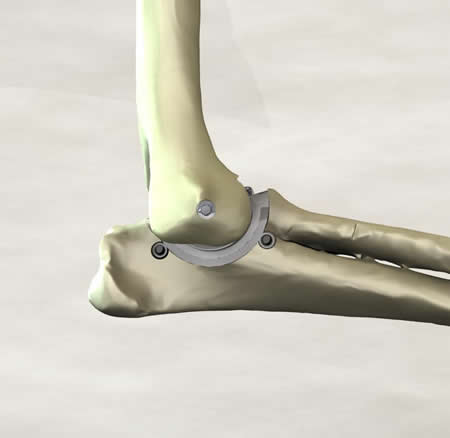

It is a minimally invasive resurfacing arthroplasty of the canine elbow.

After attending the courses and reviewing the past systems, I had some general concepts. I wanted a medial approach due to lateral luxations seen with other systems. A minimally invasive concept was essential to reduce patient morbidity and decrease the post operative aftercare. After some loose implants with cemented hip systems, I chose a non-cemented system for the elbow.

I remember the day the mill and drill concept was developed and it just felt right. We had attempted bone preparation with saws and spine burrs, and we finally started talking about milling. Custom end mills were developed and the cuts were fast and accurate. We realized that drilling for implant attachment to bone, then milling, would allow preparation of both sides of the joint simultaneously without disarticulation. The collateral ligaments were preserved in their original length with no impingement through the range of motion. The cartridge concept soon followed, and I felt we were on the way. After implanting many cadavers with different SLA prototypes, our tenth prototype felt right in the cadaver. We tested for full range of motion with stability in extension and flexion.

Simultaneous preparation of both joint surfaces using the axis of rotation as the mill datum has not been done before. The other unique aspect of the patent is inserting both components of an arthroplasty together as a cartridge. These concepts potentially provide for improved alignment of the implants, reduced surgical trauma and reduced surgical time.